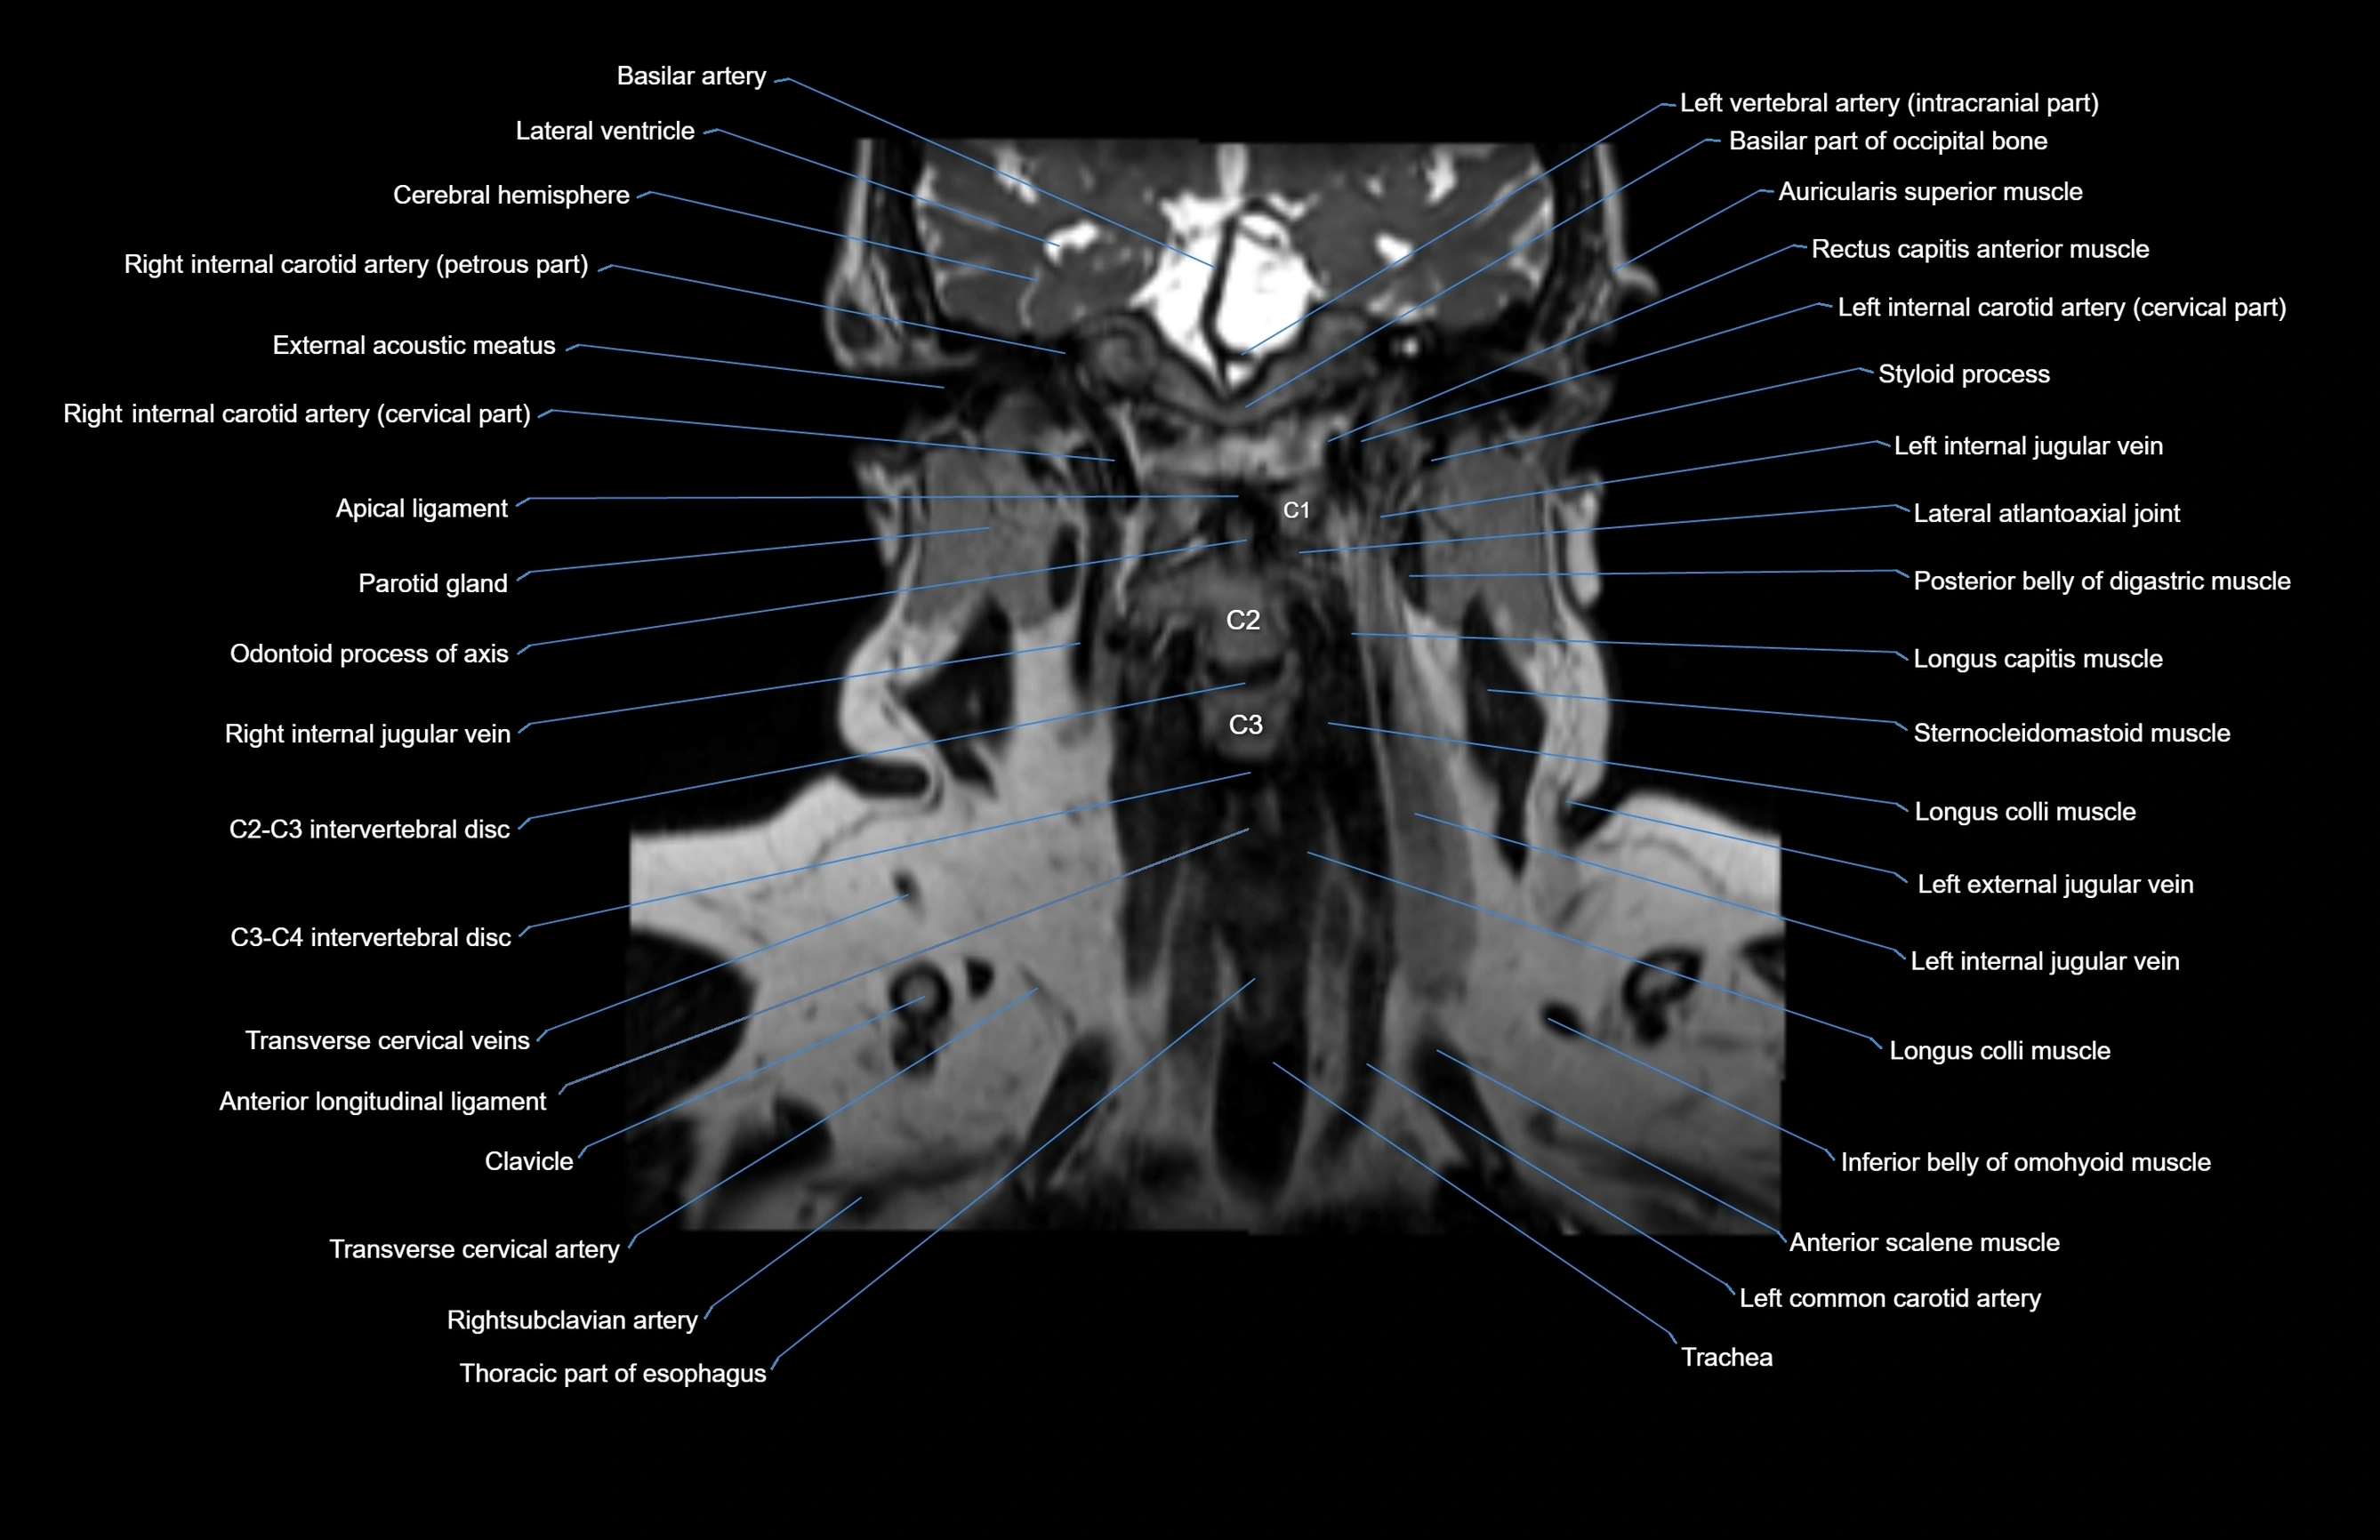

MRI images